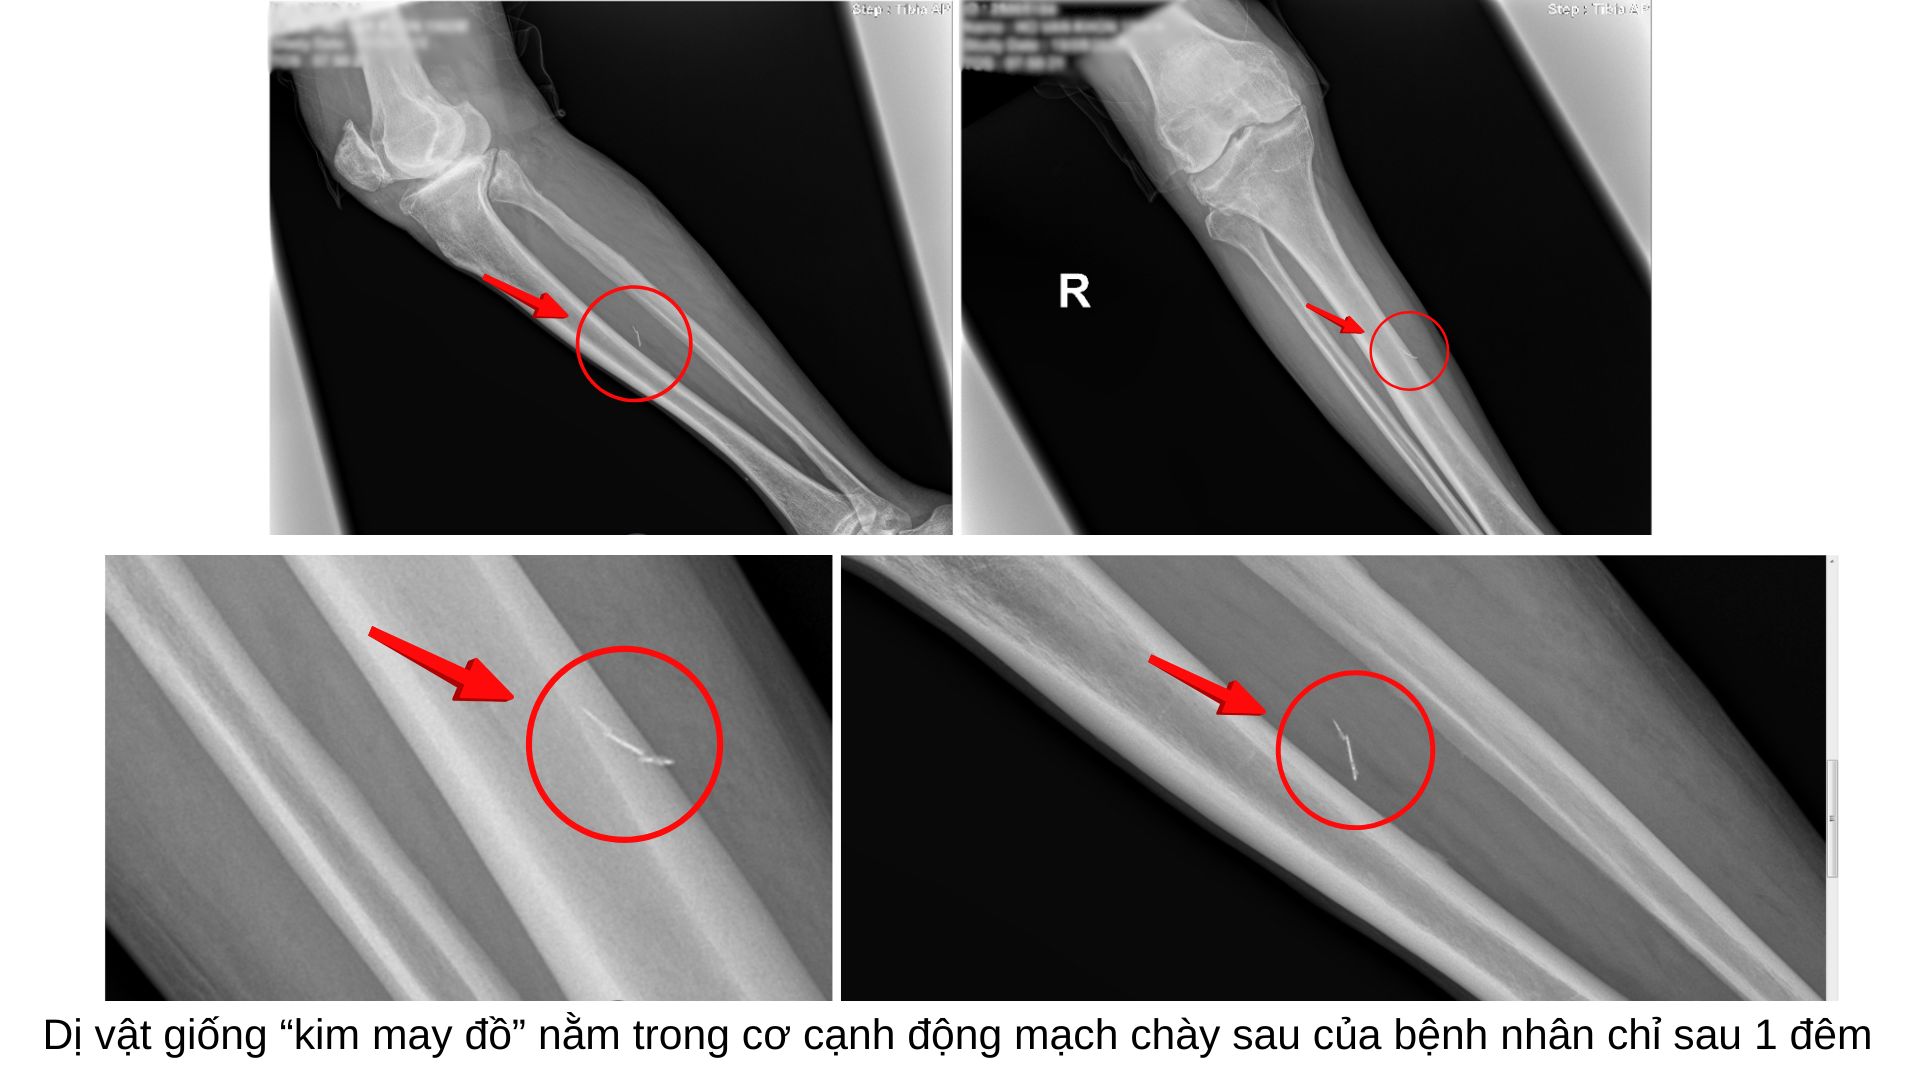

Sau khi khám lâm sàng, bác sĩ chỉ định chụp X-quang. Kết quả cho thấy có một dị vật cản quang hình dáng giống “kim may” nằm trong vùng cẳng chân phải. Điều đặc biệt là bệnh nhân hoàn toàn không hay biết về sự tồn tại hay nguyên nhân xuất hiện của dị vật này trong cơ thể.

Sau khi phát hiện qua X-quang, bệnh nhân được chỉ định siêu âm kiểm tra thêm và xác định dị vật nằm trong cơ cạnh động mạch chày sau, khu vực có mạch máu quan trọng nuôi chân. Dị vật đã gãy làm ba đoạn nhưng chưa gây viêm quanh vùng. Tuy nhiên, nếu dị vật đâm vào mạch máu, nguy cơ tụ máu chèn ép mô xung quanh hay huyết khối gây tắc mạch và nhiễm trùng là rất cao.